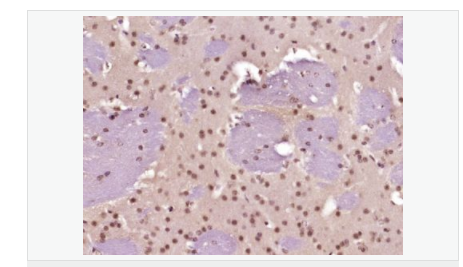

| 產(chǎn)品應(yīng)用 | WB=1:500-2000 ELISA=1:5000-10000 IHC-P=1:100-500 IHC-F=1:100-500 Flow-Cyt=1ug/Test ICC=1:100-500 IF=1:100-500 (石蠟切片需做抗原修復(fù)) not yet tested in other applications. optimal dilutions/concentrations should be determined by the end user. |

| 細(xì)胞定位 | 細(xì)胞核 |